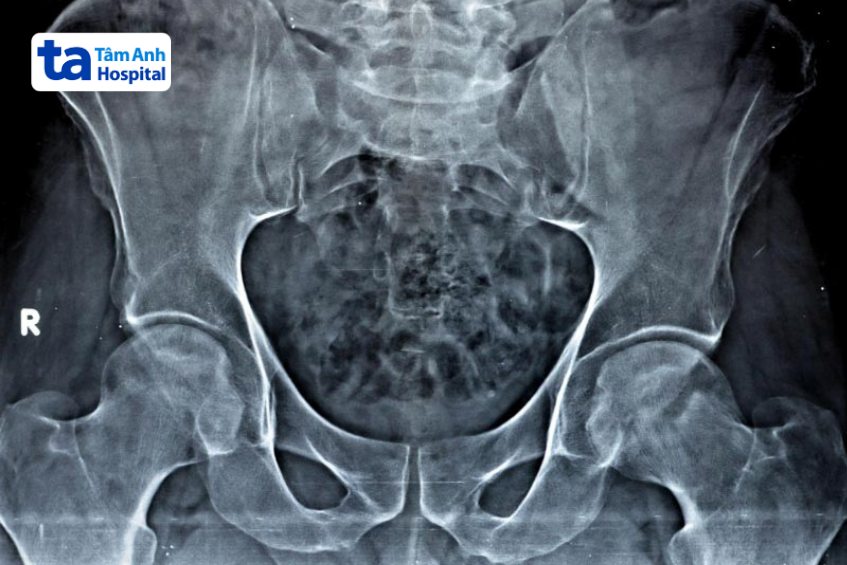

Hình ảnh viêm khớp háng trên X-quang có thể giúp bác sĩ đánh giá tình trạng và giai đoạn tiến triển của bệnh. Viêm khớp háng bao gồm 4 cấp độ tiến triển dựa vào mức độ tổn thương ở khớp háng: (1)

Chụp X-quang có thể được xem là phương pháp chẩn đoán hình ảnh viêm khớp háng đơn giản nhất và có chi phí rẻ nhất. Thông qua kết quả chụp phim X-quang, bác sĩ có thể quan sát được cấu trúc xương và tình trạng chấn thương ở các mô mềm xung quanh (nếu có). Trên phim X-quang không thể thấy được tình trạng sụn khớp, nhưng bác sĩ có thể chẩn đoán viêm khớp háng gián tiếp thông qua khoảng cách giữa xương đùi và ổ cối xương chậu.